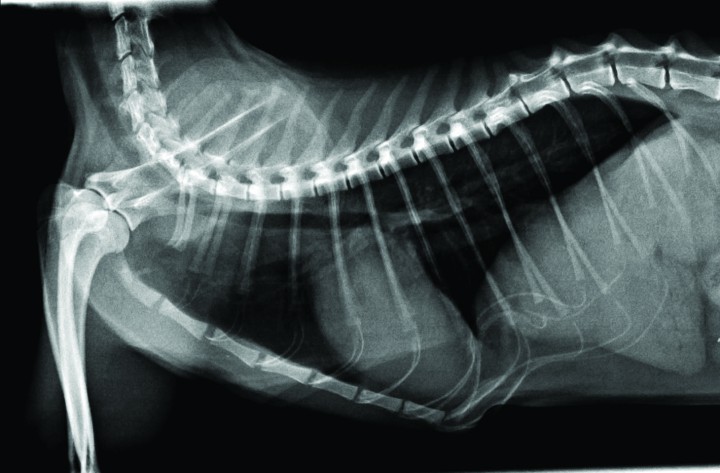

Basándonos en la lista de problemas, se realizan radiografías laterales de la cavidad torácica, cabeza y cuello. En el tórax se observa un leve aumento de tamaño de la silueta cardíaca con un “vertebral heart score” (VHS) de 8 (valores normales: 7,5±0,3) (Fig. 1). En región nasofaríngea se observa una línea de opacidad tejido blando dorsal al paladar blando y una probable elongación del paladar (Fig. 2). Se realiza también un perfil básico que incluye hematología y bioquímica séricas, estando todos los valores en rango normal. Se efectúan, además, tests serológicos para leucemia (FeLV) e inmunodeficiencia (FIV) con resultado negativo.

<p>Radiografía LL del tórax en la que se observa leve cardiomegalia.</p>

Radiografía LL del tórax en la que se observa leve cardiomegalia.